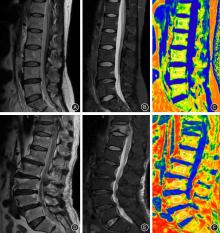

目的 探究MRI脂肪定量参数椎体骨髓脂肪分数(FF)联合25-羟基维生素D[25(OH)D]预测骨质疏松症患者骨折风险的临床应用价值。 方法 选取2023年1月至2024年4月广州医科大学附属第四医院收治的90例骨质疏松症患者为对象,将50例发生骨质疏松性椎体压缩性骨折的患者纳入骨折组,40例未发生骨折的患者纳入对照组。所有患者均接受脊柱MRI脂肪定量技术(IDEAL-IQ)扫描,测定L1~5各椎体FF及L1~5椎体平均FF,采用电化学发光法检测血清25(OH)D水平。比较两组患者FF、血清25(OH)D水平,分析FF、25(OH)D与骨密度(BMD)的相关性;多因素logistic回归分析法分析影响骨质疏松症患者骨折的危险因素,受试者工作特征曲线(ROC)评估FF、25(OH)D及其联合诊断对骨质疏松症患者骨折的预测价值。 结果 骨折组年龄大于对照组,BMD、血清25(OH)D水平低于对照组(P < 0.05)。骨折组L2椎体FF、L1~5椎体平均FF均高于对照组(P < 0.05)。相关性分析结果显示,L2椎体FF、L1~5椎体平均FF与BMD均呈负相关(P < 0.05),血清25(OH)D水平与BMD呈正相关(P < 0.05)。多因素logistic回归分析示,年龄、L2椎体FF是骨质疏松症患者骨折的独立危险因素,BMD、25(OH)D是其保护因素(P < 0.05)。ROC曲线示,L2椎体FF、25(OH)D预测骨折的AUC分别为0.714(95%CI:0.606 ~ 0.822)、0.774(95%CI:0.672 ~ 0.876),联合预测的AUC为0.923(95%CI:0.867~0.978),明显大于单一指标预测(P < 0.05)。 结论 L2椎体FF、血清25(OH)D水平与骨质疏松症患者骨折有关,与年龄、BMD共同为骨质疏松症患者并发骨折的影响因素;L2椎体FF、25(OH)D对骨质疏松症患者骨折风险具有一定预测价值,联合检测可进一步提高预测效能。

Objective To explore the clinical application value of MRI fat quantification parameter [vertebral bone marrow fat fraction (FF)] combined with 25?hydroxyvitamin D [25(OH)D] in predicting fracture risk in patients with osteoporosis. Methods A total of 90 patients with osteoporosis who were admitted to the hospital from January 2023 to April 2024 were selected as the subjects. Among them, 50 patients with osteoporotic vertebral compression fractures were included in the fracture group, and 40 patients without fractures were included in the control group. All patients underwent the iterative decomposition of water and fat with echo asymmetry and least?squares estimation (IDEAL?IQ) method of MRI to measure the FF of each vertebra among L1?5 and the average FF of L1?5. Serum 25 (OH) D level was detected by electrochemiluminescence method. FF and serum 25(OH)D levels of the two groups were compared. The correlation of FF, 25(OH)D and bone mineral density (BMD) was analyzed. Multivariate logistic regression analysis was conducted to screen the risk factors for fracture in patients with osteoporosis. Receiver operating characteristic (ROC) curves were used to evaluate the predictive value of FF, 25(OH)D, and their combination for fracture in patients with osteoporosis. Results Patients in the fracture group were older than those in the control group. BMD and serum 25(OH)D level were lower than those of the control group (P < 0.05). The FF of L2 and average FF of L1?5 in the fracture group were higher than those in the control group (P < 0.05). Correlation analysis results showed that the FF of L2 and the average FF of L1?5 were negatively correlated with BMD (P < 0.05), while serum 25 (OH) D level was positively correlated with BMD (P < 0.05). Multivariate logistic regression analysis showed that age and FF of L2 were independent risk factors for fracture in patients with osteoporosis, while BMD and 25(OH)D were protective factors (P < 0.05). ROC curves indicated that the AUC values of FF of L2 and 25(OH)D for predicting fracture were 0.714 (95% CI: 0.606 ~ 0.822) and 0.774 (95% CI: 0.672 ~ 0.876). The AUC of joint prediction was 0.923 (95% CI: 0.867 ~ 0.978), which was significantly larger than that of separate prediction (P < 0.05). Conclusions FF of L2 and serum 25(OH)D are related to fracture in patients with osteoporosis. Age and BMD are factors influencing the occurrence of fracture in patients with osteoporosis. FF of L2 and 25(OH)D have certain predictive value for fracture risk in patients with osteoporosis, and combined detection of the two can improve predictive efficiency.